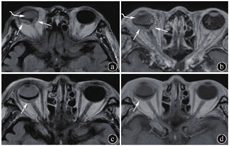

①22例(84.6%)病例为单眼受累,4例(15.4%)为双眼受累(表1)。②14例(53.8%)病例为单发病灶,12例(46.2%)为多发病灶,后者包括8例(66.7%,8/12)单眼多灶,4例(33.3%,4/12)双眼受累(图2)。③部位:位于眼球后极14例(53.8%),后极偏侧9例(34.6%),赤道部3例(11.5%)。④形态:新月形13例(50.0%),半月形2例(7.7%),梭形7例(26.9%),不规则形4例(15.4%)(图3)。⑤边界:病灶内侧缘边界清楚18例(69.2%),模糊8例(30.8%)。⑥最大厚度:2~9mm,平均(4.2±1.8)mm。⑦信号与强化特征:以同层眼肌作为参照,病灶于T1WI呈等信号22例(84.6%),稍高信号4例(15.4%);于T2WI或FLAIR序列呈高或稍高信号17例(65.4%),等信号3例(11.5%),混杂信号6例(23.1%)。增强扫描明显强化16例(61.5%),中等强化8例(30.8%),轻度强化2例(7.7%)。强化均匀19例(73.1%),强化不均匀7例(26.9%)(图4)。

注:患者肺癌术后化疗后4年,视力下降1周,视网膜脱离术后。图a为平扫液体衰减反转恢复(FLAIR)序列,图b为增强扫描T1加权像(T1WI)。见右侧眼球后极偏侧两个梭形病灶,FLAIR呈稍高信号,增强扫描中等均匀强化(直箭),另可见继发右侧晶状体混浊(弯箭)。图c、d分别为化疗+局部放疗后FLAIR序列及增强扫描T1WI,见病灶有缩小,但仍可见肿瘤残存(直箭)。